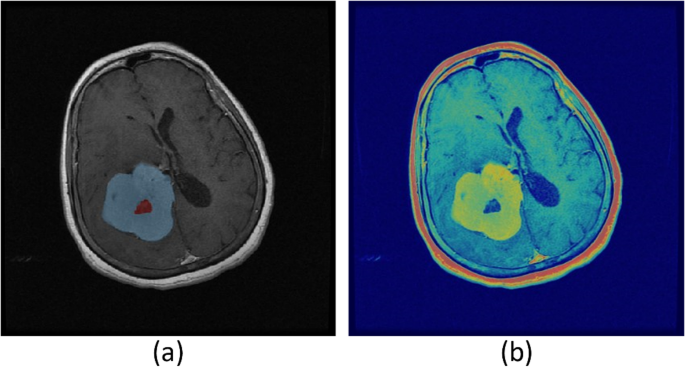

Sophisticated algorithms were meticulously crafted to extract intricate features from the PET and MRI image datasets, facilitating a comprehensive analysis of the distinctive characteristics and commonalities in tumor features. A central focus of this investigation was to evaluate the degree of tumor volume overlap (referred to as Voverlap) observed in both modalities. Precisely quantifying Voverlap entailed assessing the segmented volume shared by the VPET and VMR images. Furthermore, the analysis encompassed discerning the distinct volumes unique to each modality, denoted as VonlyPET and VonlyMR, respectively. It is crucial to comprehend that PET imaging enables the acquisition of information at an earlier stage in tumor development compared to MRI. Thus, VonlyPET signifies the tumor exhibiting active growth discernible solely through PET imaging, not yet manifest in MRI. Similarly, VonlyMR represents the active and necrotic tumor volume exclusively visualized through MRI imaging. By judiciously amalgamating the segmented volumes attributed to either VPET or VMR or both, their volume of tumor in combination, portrayed in MR and PET images can be ascertained. This comprehensive information significantly contributes to a more profound understanding of tumor growth dynamics and provides crucial insights into potential avenues for treatment optimization. The segmentation of tumor volumes across PET and MR modalities provides valuable insights into spatial overlap and modality-specific differences. As illustrated in Fig. 6, the segmented volumes for PET and MR are displayed, highlighting their spatial overlap (Voverlap) as well as unique volumes identified exclusively by each modality (VonlyPET and VonlyMR). This comparison underscores the complementary nature of PET and MR imaging for comprehensive tumor characterization.

Figure 7 exhibits a meticulously selected axial slice of the brain, ingeniously captured utilizing MRI with contrast enhancement. This striking visualization distinctly showcases the derived tumor volumes, meticulously delineating the distinct regions exclusively revealed through PET imaging (referred to as PET-only), the unique areas solely visible in MR imaging (referred to as MR-only), and the captivating overlapping tumor volumes that are prominently observed in both modalities. This comprehensive illustration provides a profound visual representation of the intricate interplay between PET and MR imaging in capturing and characterizing tumor volumes, thereby enriching our understanding of the multifaceted nature of these tumors.